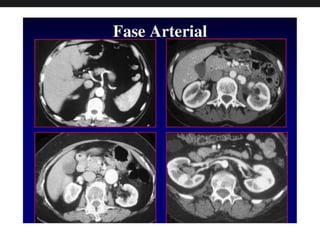

Fase Arterial

• É a fase de contraste com a concentração do MC nos

seguimentos arteriais. Aproximadamente 20 cortes no

abdome superior, varrendo-se em aquisição helicoidal,

com cortes de 10 mm de espessura. Após o início da

infusão do meio de contraste, a fase arterial poderá ser

obtida entre 30 e 40 segundos.